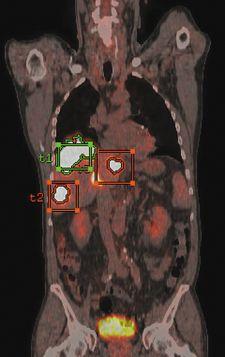

GE Healthcare has received FDA clearance for the next-generation volume PET/CT application, PET VCAR (Volume Computer-Assisted Reading). It was created to help clinicians diagnose, stage, treat and monitor tumors and other lesions in the body.

PET VCAR offers several workflow enhancements for both single and multi-exam review, including exam-to-exam automatic registration, tumor segmentation and quantification and multi-planar image review.

The FDA clearance includes a GE-patent Interactive Data Analysis (IDA) tool, which allows physicians to systematically track treatment over time and quantitatively interpret a patient’s response to therapy. The new IDA capability reportedly facilitates informed, objective treatment decision making by automating several previously manual processes and presenting data in an organized, user-configurable format.